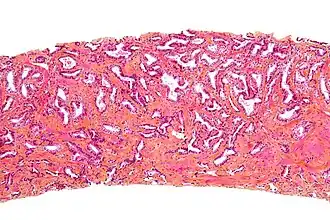

![]() Micrografía de próstata que muestra una biopsia de próstata adenocarcinoma, el tipo acinar, el tipo más común de cáncer de próstata. | ||